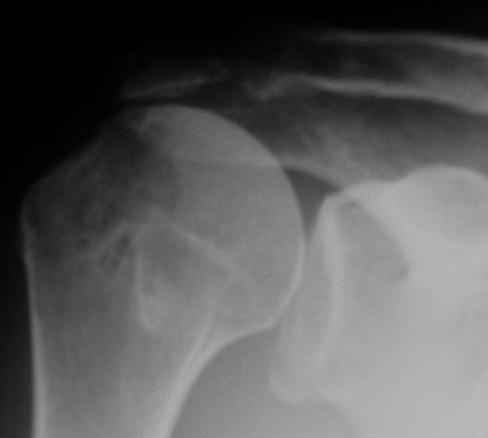

В качестве примера - снимки до и после восстановления целостности вращательной манжеты после 3-хмесячной давности полного разрыва. Видно, что верхний подвывих устранен.